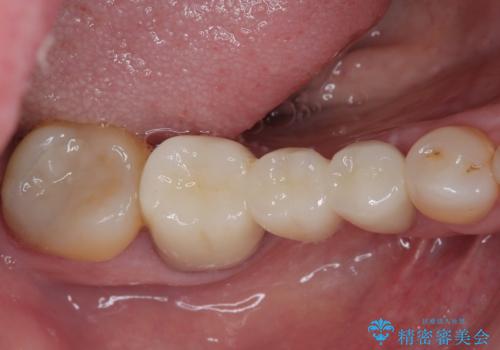

欠損の多い奥歯 インプラントによる補綴治療

右下の銀歯も気になるとのことで、インプラント治療と並行してオールセラミックによるブリッジ補綴治療も行うこととしました。

地元に戻られる前に無事に治療を終えることができました。

今後は東京出張のタイミングでメインテナンスに通院していただきながら、インプラントの状態をチェックしていくことになります。